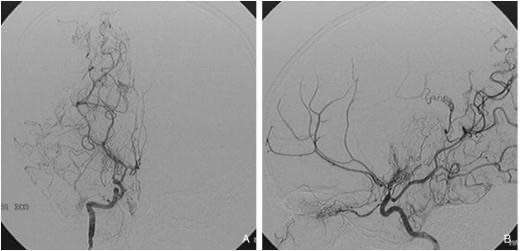

모야모야병은 뇌기저부의 주요 혈관이 서서히 협착되고 막히면서 뇌혈류가 감소하는 만성 진행성 뇌혈관 질환입니다. 협착이 진행된 부위를 대신해 뇌는 생존을 위해 얇고 약한 혈관망을 만들어 혈류를 보충하려 하고, 이 새로운 혈관들이 촬영 영상에서 연기처럼 퍼져 보인다고 하여 ‘모야모야’라는 이름이 붙었습니다. 기전적으로는 내경동맥 말단부와 중대뇌동맥·전대뇌동맥의 기시부에 병변이 가장 잘 생기며, 시간이 지남에 따라 양쪽에 대칭적으로 나타나는 특징을 보였습니다. 이 질환은 단순한 혈관 협착이 아니라 진행성 변화이기 때문에 치료하지 않으면 혈류 부족이 심해지고 뇌 손상이 누적될 수 있습니다. 또한 뇌기능이 체력·호흡·체온 변화 등에 민감하게 반응하기 때문에 과호흡, 울음, 격렬한 운동, 감염 등으로 증상이 악화될 수 있습니다. 즉, 모야모야병은 시간이 지나면서 뇌혈류를 감소시키고 뇌졸중 위험을 높이는 질환이며, 평생 관리가 필요한 만성적 특성을 갖고 있습니다.

① 직접 우회술(Direct bypass)

• 측두동맥(STA)을 직접 뇌혈관(MCA)과 연결해 혈류를 즉시 공급하는 방식 • 성인에서 가장 많이 시행

• 수술 직후부터 혈류 개선 효과가 빠르게 나타납니다.

② 간접 우회술(Indirect bypass)

• 근육이나 막 조직을 뇌 표면에 붙여 그 조직에서 자라는 새로운 혈관이 뇌를 공급하도록 유도 • 소아에서 많이 사용

• 혈류 증가 효과가 나타나기까지 수개월이 필요합니다.

③ 혼합 우회술(Combined bypass)

• 직접 + 간접 방법을 동시에 시행하는 방식

• 빠른 효과 + 장기 안정성을 동시에 노릴 수 있는 방법입니다.